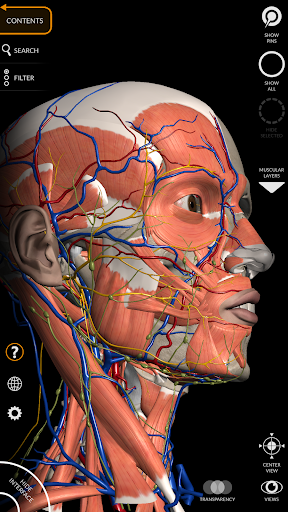

"Anatomy 3D Atlas" memungkinkan Anda mempelajari anatomi manusia dengan cara yang mudah dan interaktif.

Melalui antarmuka yang sederhana dan intuitif, Anda dapat mengamati setiap struktur anatomi dari sudut mana pun.

Model 3D anatomi sangat terperinci dan memiliki tekstur hingga resolusi 4k.

Pembagian berdasarkan wilayah dan tampilan yang telah ditetapkan sebelumnya memudahkan pengamatan dan studi bagian tunggal atau kelompok sistem dan hubungan antara organ yang berbeda.

MODEL ANATOMI 3D

• Sistem muskuloskeletal

saraf • Sistem pernapasan • Sistem pencernaan • Sistem urogenital (pria dan wanita) • Sistem endokrin • Sistem limfatik • Sistem mata dan telinga FITUR • Antarmuka yang sederhana dan intuitif • Putar dan perbesar setiap model dalam ruang 3D • Opsi untuk menyembunyikan atau mengisolasi satu atau beberapa model yang dipilih • Filter untuk menyembunyikan atau menampilkan setiap sistem • Fungsi pencarian untuk menemukan setiap bagian anatomi dengan mudah • Fungsi penanda untuk menyimpan tampilan khusus • Rotasi cerdas yang menggerakkan pusat rotasi secara otomatis • Fungsi transparansi • Visualisasi otot melalui tingkat lapisan dari yang superfisial hingga yang terdalam • Dengan memilih model atau pin, istilah anatomi terkait akan muncul • Deskripsi otot: asal, • Tampilkan/ Sembunyikan antarmuka UI (sangat berguna dengan layar kecil) MULTIBAHASA • Istilah anatomi dan antarmuka pengguna tersedia dalam 11 bahasa: Latin, Inggris, Prancis, Jerman, Italia, Portugis, Turki, Rusia, Spanyol, Mandarin, Jepang, dan Korea • Istilah anatomi dapat ditampilkan dalam dua bahasa secara bersamaan PERSYARATAN SISTEM • Android 8.0 atau yang lebih baru, perangkat dengan RAM minimal 3GB Reversi